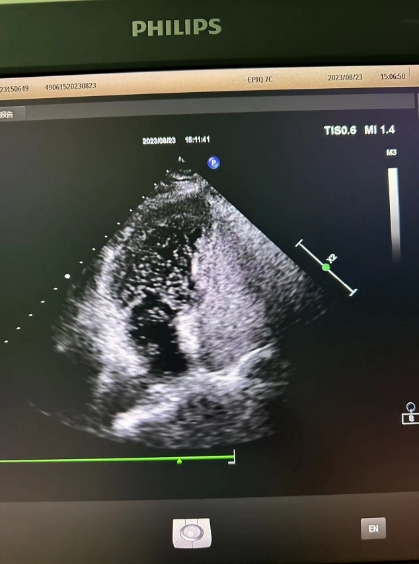

超聲心動圖檢查發(fā)現(xiàn)可能存在卵圓孔未閉,經(jīng)心內(nèi)科會診,詳細(xì)詢問病情、仔細(xì)了解病史后,為進(jìn)一步明確診治,決定為患者進(jìn)行右心聲學(xué)造影檢查。右心聲學(xué)造影是一項無創(chuàng)、便捷的超聲檢查技術(shù),醫(yī)護(hù)人員首先在患者胳臂上建立一個靜脈通路,然后把含有微小氣泡的振蕩生理鹽水注入患者體內(nèi),同時將超聲探頭放在患者心前區(qū),借助超聲檢查設(shè)備,觀察進(jìn)入人體心腔的微小氣泡運動情況。

患者檢查后果然發(fā)現(xiàn)了異常,從屏幕上可以清晰看到,患者左心房內(nèi)很快出現(xiàn)了大量微小氣泡,這說明該患者的心臟存在著房水平由右向左的分流,提示有先天性卵圓孔未閉!根據(jù)這一檢查結(jié)果與患者及家屬溝通后,心內(nèi)科為其進(jìn)行了卵圓孔未閉封堵術(shù),最終改善了患者多年來的頭暈頭痛癥狀。